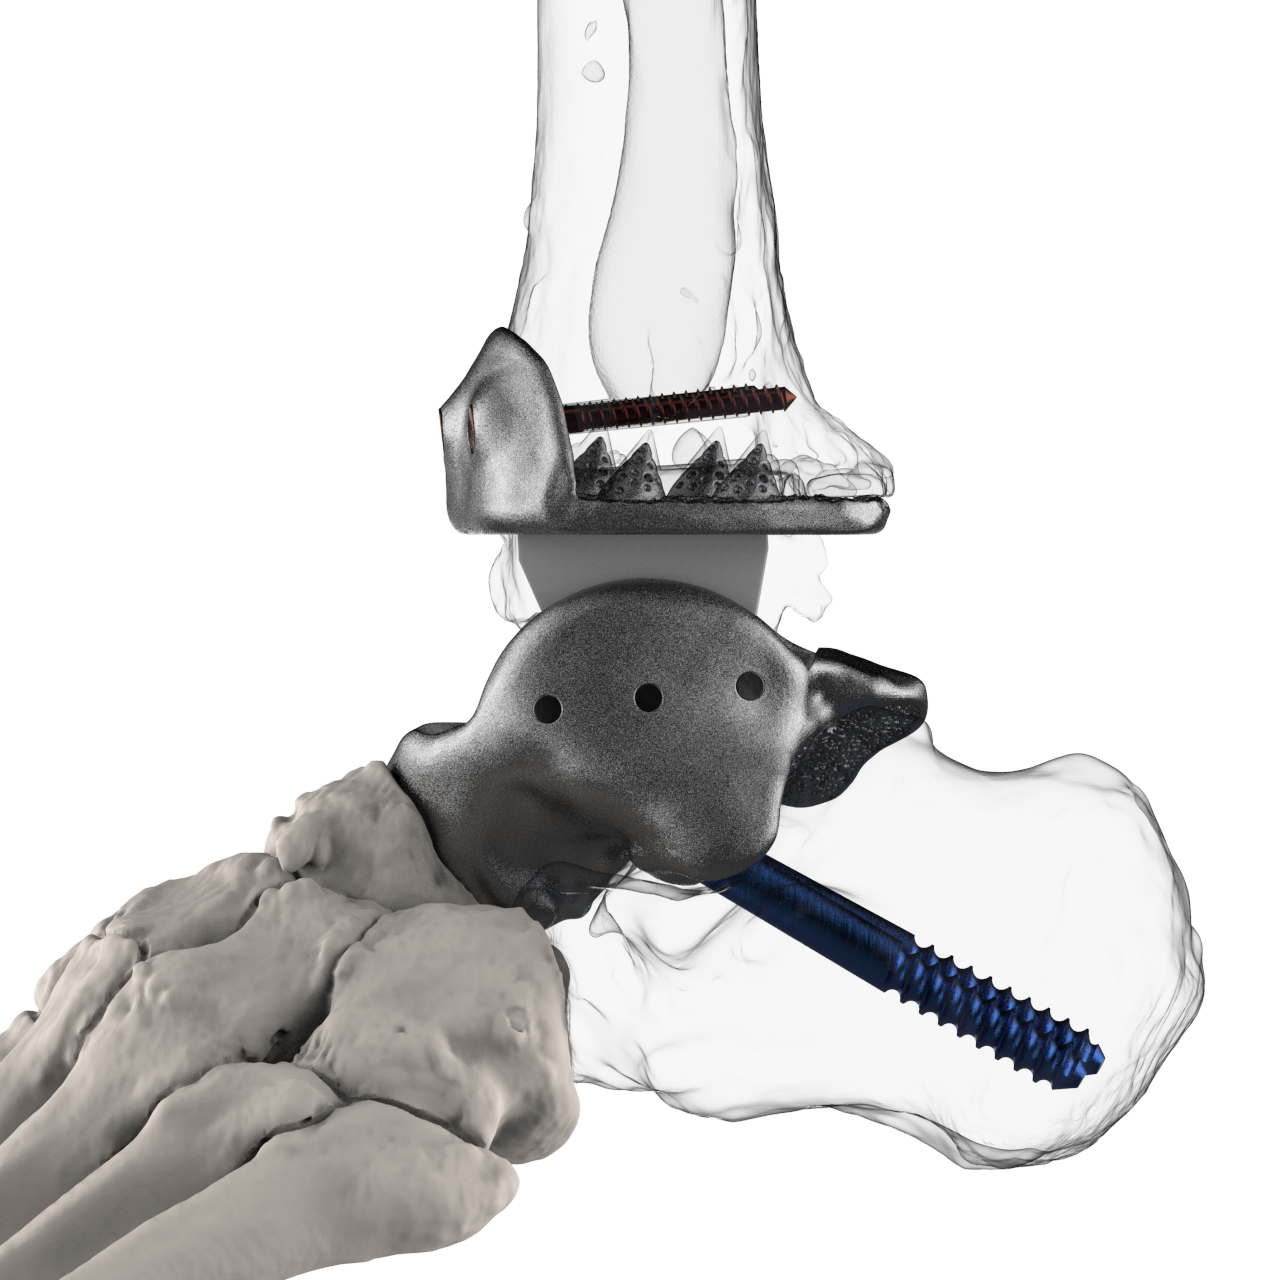

Patient-specific equipment and systems

Patient-specific equipment (such as hearing aids) and implants (such as artificial limbs, cranial plates, and even heart valves) are increasingly turning to 3D printing for rapid modification and accelerated development.

There are design advantages too: 3D printed silicone heart valves have the perfect match that rigid, commonly designed heart valves simply can’t. For implants such as titanium artificial joints or cranial plates, the services of 3D printing companies can produce intricate and porous surfaces that make patients’ bodies less likely to resist implants.